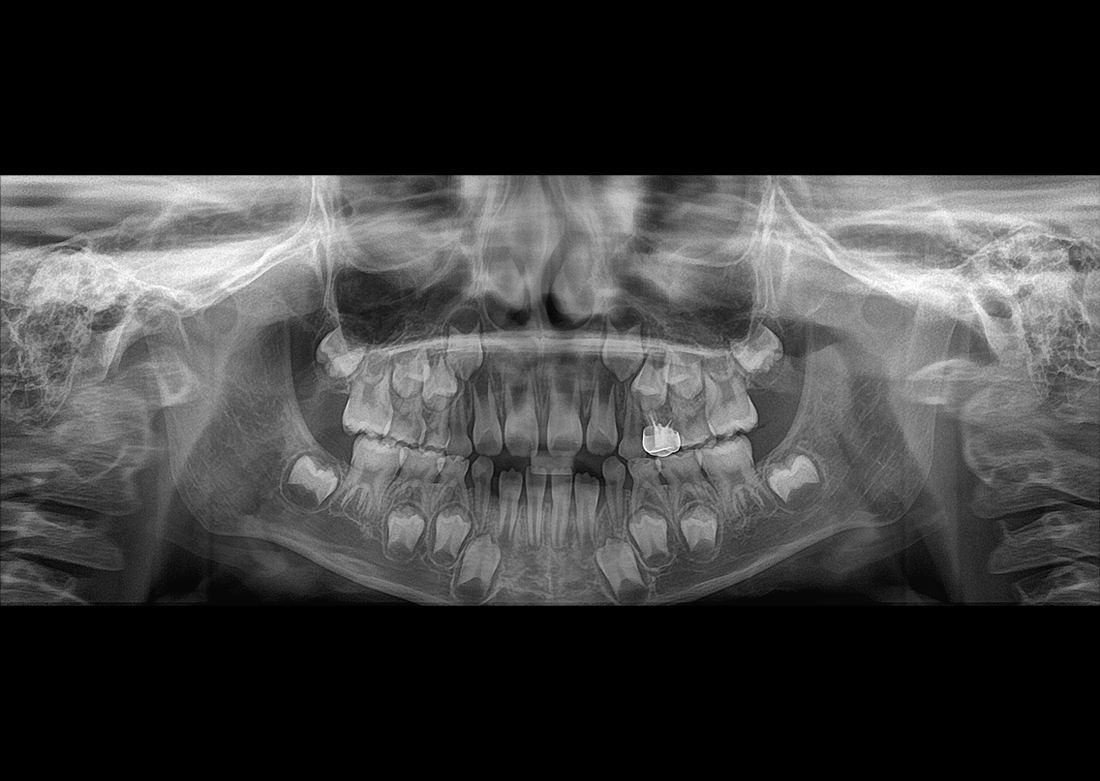

KLİNIKAI KÉPEK

Kiváló diagnosztikai képalkotás több éves tapasztalattal és szakértelemmel.

A Genoray büszkesége, amelyet világszerte elismernek és szeretnek.